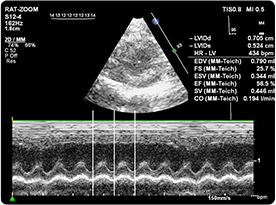

四維全數(shù)字彩色多普勒 超聲診斷系統(tǒng)

超聲成像技術(shù)是利用超聲波的物理特性和動(dòng)物體器官組織聲學(xué)特性相互作用后產(chǎn)生的信息,經(jīng)信息處理形成圖像的成像技術(shù)。

動(dòng)物體結(jié)構(gòu)對(duì)于超聲而言是一個(gè)復(fù)雜的介質(zhì),各種器官與組織(包括病理組織)都有它特定的聲像阻抗和衰減特性,因而構(gòu)成聲阻抗上的差別和衰減上的差異,這種不同的反射與衰減構(gòu)成了超聲圖像的基礎(chǔ)。因而根據(jù)顯示和記錄的波形、曲線或圖像的形式,借以進(jìn)行集體的檢查和疾病的診斷。

| 超聲儀(含氣麻費(fèi)用) | 450 | 元/只/次,單次5只起做 | 心超(射血分?jǐn)?shù)EF,縮短分?jǐn)?shù)FS,收藏末期直徑LVESD、舒張末期直徑LVEDD、收縮期容積LVVS、舒張期容積LVVD) |

可應(yīng)用方向

寵物妊娠診斷

寵物膀胱尿道腎膽的結(jié)石

子宮積液(濃)

腎盂積液

泌尿

腹水以及肝膽

前列腺腫大

生殖系統(tǒng)的疾病及其他實(shí)質(zhì)性器官疾病的輔助診斷與治療